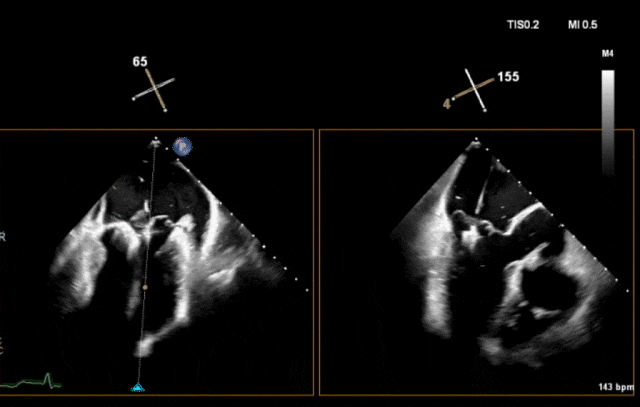

接下来术者着手干预三尖瓣,三尖瓣夹合器送入右心房后,术者调整系统轴向使夹合器指向三尖瓣,夹合器顺利跨越三尖瓣。

图片

夹合器跨瓣

夹合器跨瓣后,术者精细调整夹合器位置,打开、回拉夹合器捕获三尖瓣前叶和隔叶,超声示前叶、隔叶受限,三尖瓣残余反流1+,考虑到患者合并肺动脉高压,残留部分反流能降低肺动脉高压加重风险,故完全释放夹合器,复查超声示三尖瓣夹合器稳定性良好,手术圆满成功!

捕获前叶和隔叶